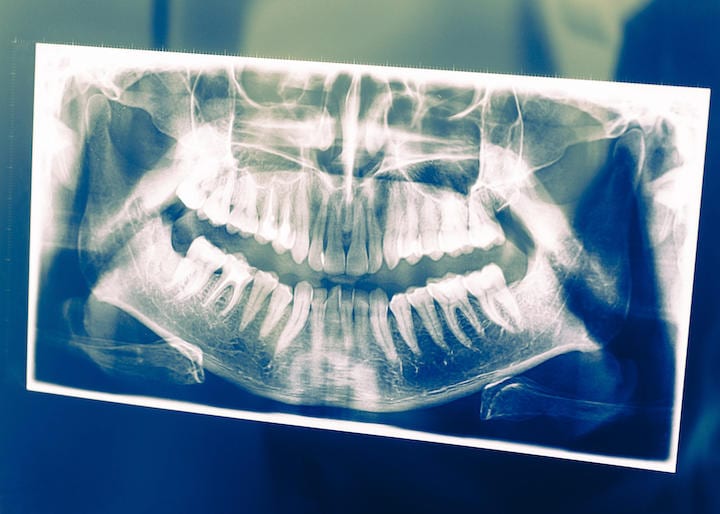

<慢性歯周炎の原因細菌であるポルフィロモナス・ジンジバリス菌がアルツハイマー病患者の脳内で確認されたという研究は発表された>

米ルイビル大学のヤン・ポテンパ博士らの研究チームは、2019年1月23日、オープンアクセスジャーナル「サイエンス・アドバンシーズ」において、「慢性歯周炎の原因細菌であるポルフィロモナス・ジンジバリス菌がアルツハイマー病患者の脳内で確認された」との研究論文を公開した。